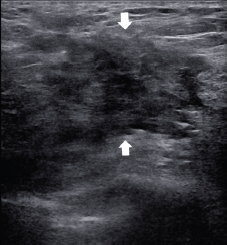

Frequently the diagnosis is performed with ultrasound biopsy [12, 13]: heterogenous echo patterns and marked low attenuation, with ill-defined margins, are the typical ultrasound features as shown in Figures 3 and 4.

Figure 3. A 55-year-old patient presenting a right unilateral breast mass subsequently identified as a MS. (a): The heterogeneous echo patterns and marked low attenuation, with ill-defined margins (arrow). (b): The biopsy of the lesion with the needle inside the lesion (arrowhead).

Figure 4. A 60-year-old patient presenting a right unilateral breast mass subsequently identified as a MS. The heterogeneous echo patterns and marked low attenuation are appreciated, with ill-defined margins (arrows).